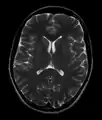

MRI image of the surface of the brain.